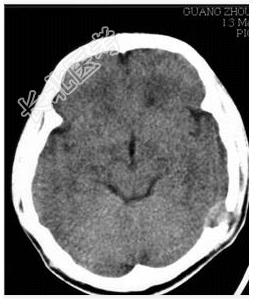

- [材料题] 病历摘要:男性,20岁。

主诉:发现头皮软组织肿物3个月。

现病史:三月前发现左枕部软组织轻微突起伴隐痛,到当地医院检查发现左枕部颅骨骨质缺损,未作具体治疗,现觉头皮肿物增大,时伴有气促、头痛。

专科检查:左颞枕部软组织略膨起,较软,各项病理反射(-)。